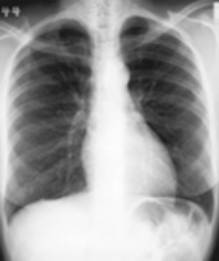

RX thorax

Dit is het meest uitgevoerde onderzoek op de dienst radiologie. Een thoraxfoto kan om veel redenen worden aangevraagd.

Er zijn in principe twee manieren om een thorax opname te maken:

![]() | De staande opname waar meestal een face en een profiel opname wordt genomen |

![]() | De liggende opname bij een patiënt die niet kan staan, normaal enkel face opname tenzij anders aangevraagd |